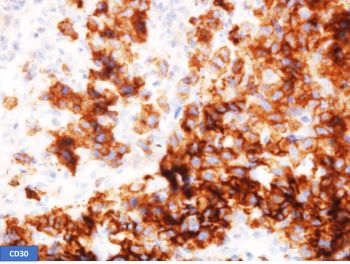

A 52-year-old man with HIV presents with weight loss and supraclavicular mass. Biopsy shows large, atypical cells with the following phenotype: CD45+, CD20-, PAX5 weak, CD3-, CD15-, CD138-, EBER-ISH+. H&E and stains for CD30 and CD79a are shown.

This is a case of EBV-positive diffuse large B-cell lymphoma associated with immune deficiency with an unusual phenotype. B-cell markers are downregulated with negative CD20 and weak expression of PAX5 and CD79a. The unusual phenotype combined with CD30 positivity raises the possibility of Classic Hodgkin lymphoma (CHL). However, the neoplastic cells are positive for CD45 and negative for CD15, making CHL unlikely. Plasmablastic lymphoma was excluded by CD138 negativity.